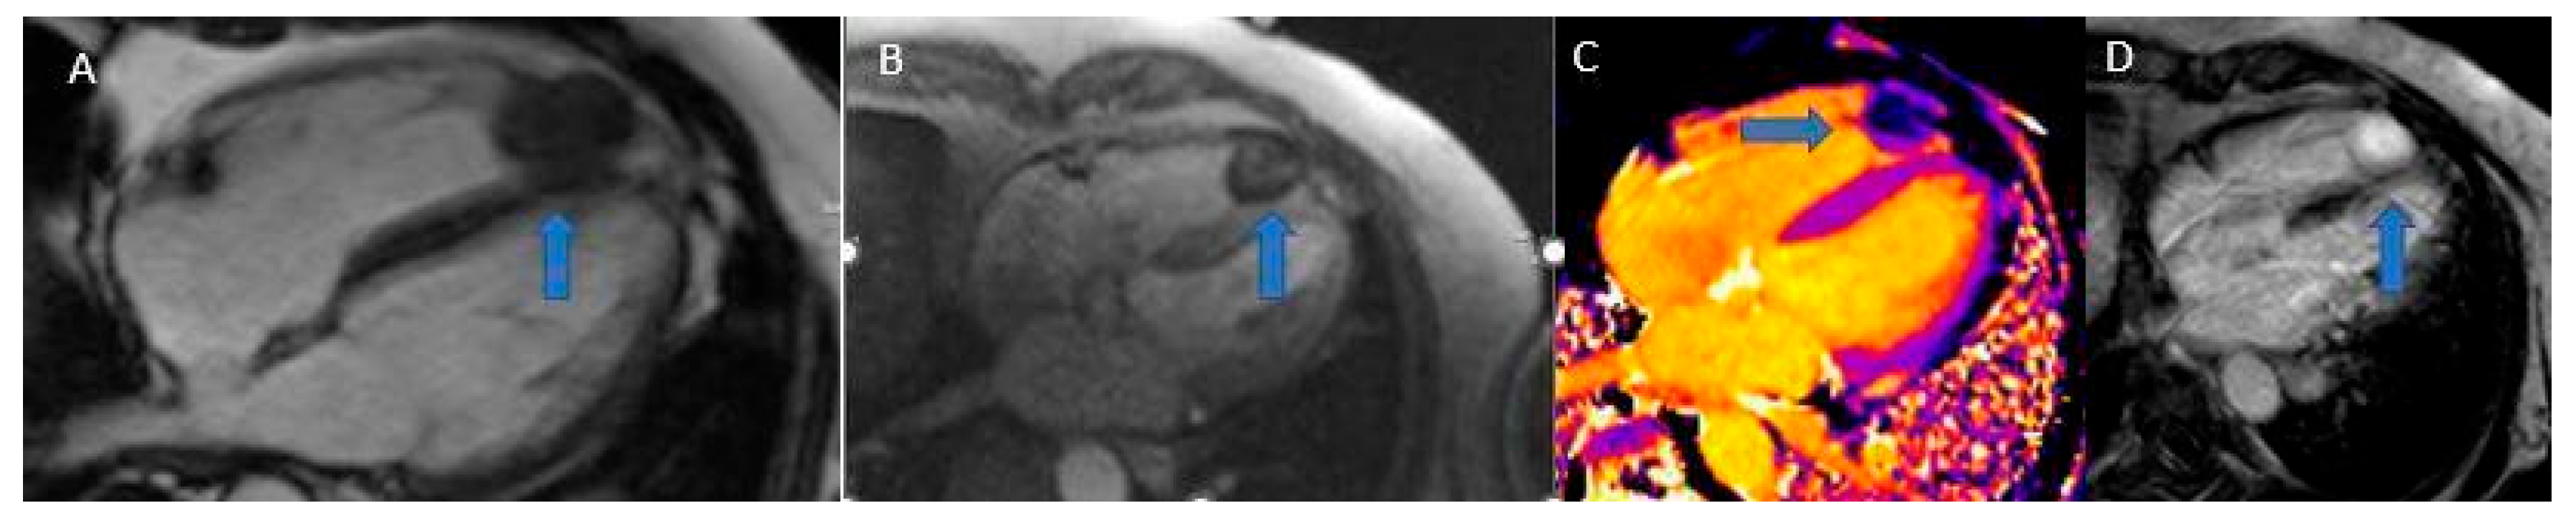

Cardiac fibromas (Figure 10) are composed of fibroblasts surrounded by large quantities of collagen, forming a well-defined, solitary, endomyocardial tumor mass with smooth edges, usually greater than 5 cm in diameter, and can even obliterate the entire ventricular cavity. They most commonly originate from the free wall of the left ventricle, the interventricular septum, or the free wall of the right ventricle. Although cystic foci, hemorrhages, or necrosis are rare, calcifications are commonly found and are a typical manifestation of Gorlin syndrome [3,44].

On CT, fibromas appear as homogeneous masses with a density similar to cardiac muscle, rarely infiltrative, with homogeneous or finely inhomogeneous contrast enhancement. In MRI, due to their fibrotic and dense nature, fibromas usually appear hypointense on T2-weighted images and relatively isointense to cardiac muscle on T1-weighted images [3,45].

These tumors are typically homogeneous, poorly vascularized lesions that show minimal early contrast uptake yet stand out as marked hyperenhancement on late gadolinium sequences [3].

Figure 10. Fibroma (blue arrows): Cine SSFP (A), Perfusion (B), T1 mapping (C), LGE (D). Note the low contrast uptake in perfusion with higher signal intensity in LGE, typical of a fibrotic formation.